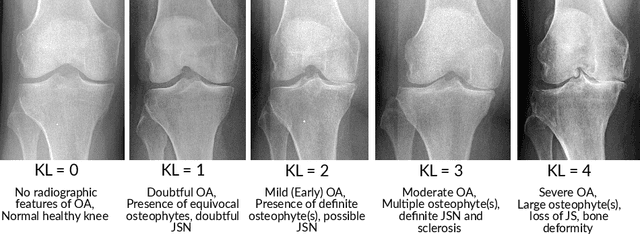

Abstract:Objective is to assess the ability of texture features for detecting radiographic patellofemoral osteoarthritis (PFOA) from knee lateral view radiographs. We used lateral view knee radiographs from MOST public use datasets (n = 5507 knees). Patellar region-of-interest (ROI) was automatically detected using landmark detection tool (BoneFinder). Hand-crafted features, based on LocalBinary Patterns (LBP), were then extracted to describe the patellar texture. First, a machine learning model (Gradient Boosting Machine) was trained to detect radiographic PFOA from the LBP features. Furthermore, we used end-to-end trained deep convolutional neural networks (CNNs) directly on the texture patches for detecting the PFOA. The proposed classification models were eventually compared with more conventional reference models that use clinical assessments and participant characteristics such as age, sex, body mass index(BMI), the total WOMAC score, and tibiofemoral Kellgren-Lawrence (KL) grade. Atlas-guided visual assessment of PFOA status by expert readers provided in the MOST public use datasets was used as a classification outcome for the models. Performance of prediction models was assessed using the area under the receiver operating characteristic curve (ROC AUC), the area under the precision-recall (PR) curve-average precision (AP)-, and Brier score in the stratified 5-fold cross validation setting.Of the 5507 knees, 953 (17.3%) had PFOA. AUC and AP for the strongest reference model including age, sex, BMI, WOMAC score, and tibiofemoral KL grade to predict PFOA were 0.817 and 0.487, respectively. Textural ROI classification using CNN significantly improved the prediction performance (ROC AUC= 0.889, AP= 0.714). We present the first study that analyses patellar bone texture for diagnosing PFOA. Our results demonstrates the potential of using texture features of patella to predict PFOA.

Abstract:Objective: To assess the ability of imaging-based deep learning to predict radiographic patellofemoral osteoarthritis (PFOA) from knee lateral view radiographs. Design: Knee lateral view radiographs were extracted from The Multicenter Osteoarthritis Study (MOST) (n = 18,436 knees). Patellar region-of-interest (ROI) was first automatically detected, and subsequently, end-to-end deep convolutional neural networks (CNNs) were trained and validated to detect the status of patellofemoral OA. Patellar ROI was detected using deep-learning-based object detection method. Manual PFOA status assessment provided in the MOST dataset was used as a classification outcome for the CNNs. Performance of prediction models was assessed using the area under the receiver operating characteristic curve (ROC AUC) and the average precision (AP) obtained from the precision-recall (PR) curve in the stratified 5-fold cross validation setting. Results: Of the 18,436 knees, 3,425 (19%) had PFOA. AUC and AP for the reference model including age, sex, body mass index (BMI), the total Western Ontario and McMaster Universities Arthritis Index (WOMAC) score, and tibiofemoral Kellgren-Lawrence (KL) grade to predict PFOA were 0.806 and 0.478, respectively. The CNN model that used only image data significantly improved the prediction of PFOA status (ROC AUC= 0.958, AP= 0.862). Conclusion: We present the first machine learning based automatic PFOA detection method. Furthermore, our deep learning based model trained on patella region from knee lateral view radiographs performs better at predicting PFOA than models based on patient characteristics and clinical assessments.

Abstract:Knee osteoarthritis (OA) is very common progressive and degenerative musculoskeletal disease worldwide creates a heavy burden on patients with reduced quality of life and also on society due to financial impact. Therefore, any attempt to reduce the burden of the disease could help both patients and society. In this study, we propose a fully automated novel method, based on combination of joint shape and convolutional neural network (CNN) based bone texture features, to distinguish between the knee radiographs with and without radiographic osteoarthritis. Moreover, we report the first attempt at describing the bone texture using CNN. Knee radiographs from Osteoarthritis Initiative (OAI) and Multicenter Osteoarthritis (MOST) studies were used in the experiments. Our models were trained on 8953 knee radiographs from OAI and evaluated on 3445 knee radiographs from MOST. Our results demonstrate that fusing the proposed shape and texture parameters achieves the state-of-the art performance in radiographic OA detection yielding area under the ROC curve (AUC) of 95.21%

Abstract:The purposes of this study were to investigate: 1) the effect of placement of region-of-interest (ROI) for texture analysis of subchondral bone in knee radiographs, and 2) the ability of several texture descriptors to distinguish between the knees with and without radiographic osteoarthritis (OA). Bilateral posterior-anterior knee radiographs were analyzed from the baseline of OAI and MOST datasets. A fully automatic method to locate the most informative region from subchondral bone using adaptive segmentation was developed. We used an oversegmentation strategy for partitioning knee images into the compact regions that follow natural texture boundaries. LBP, Fractal Dimension (FD), Haralick features, Shannon entropy, and HOG methods were computed within the standard ROI and within the proposed adaptive ROIs. Subsequently, we built logistic regression models to identify and compare the performances of each texture descriptor and each ROI placement method using 5-fold cross validation setting. Importantly, we also investigated the generalizability of our approach by training the models on OAI and testing them on MOST dataset.We used area under the receiver operating characteristic (ROC) curve (AUC) and average precision (AP) obtained from the precision-recall (PR) curve to compare the results. We found that the adaptive ROI improves the classification performance (OA vs. non-OA) over the commonly used standard ROI (up to 9% percent increase in AUC). We also observed that, from all texture parameters, LBP yielded the best performance in all settings with the best AUC of 0.840 [0.825, 0.852] and associated AP of 0.804 [0.786, 0.820]. Compared to the current state-of-the-art approaches, our results suggest that the proposed adaptive ROI approach in texture analysis of subchondral bone can increase the diagnostic performance for detecting the presence of radiographic OA.